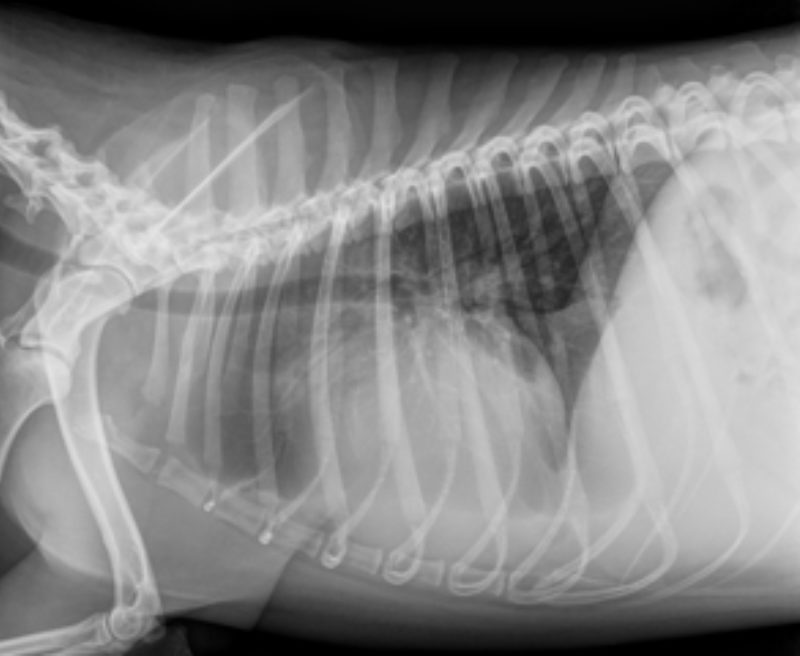

Die Besitzerin berichtete, dass „Timmi“ beim Einladen in das Auto kurz zusammengebrochen sei und sich sein Zustand bei der Anfahrt noch weiter verschlechtert hätte. In der Untersuchung war der Hund sehr matt und atmete verstärkt (Bild 1). Neben blassen Schleimhäuten und einem schwachen Puls war vor allem eine deutlich erhöhte Herzfrequenz bei eher leisen Herztönen auffällig. Eine Röntgenaufnahme des Brustkorbes zeigte eine deutlich vergrößerte und abgerundete Herzsilhouette und führte zu dem Verdacht eines Herzbeutelergusses (Bild 2). Zur weiteren Abklärung wurde ein Herzultraschall durchgeführt, womit die Verdachtsdiagnose schnell bestätigt werden konnte (Bild 3).